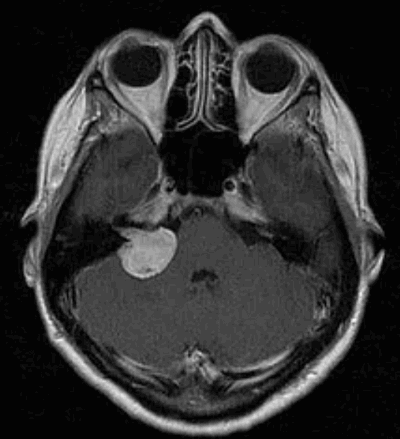

Двусторонние, асимметричного размера (S>D) акустические

шванномы, ассоциированные с нейрофиброматозом II типа.

На рис.818 визуализируются менингиомы, также

ассоциированные с НФ II.